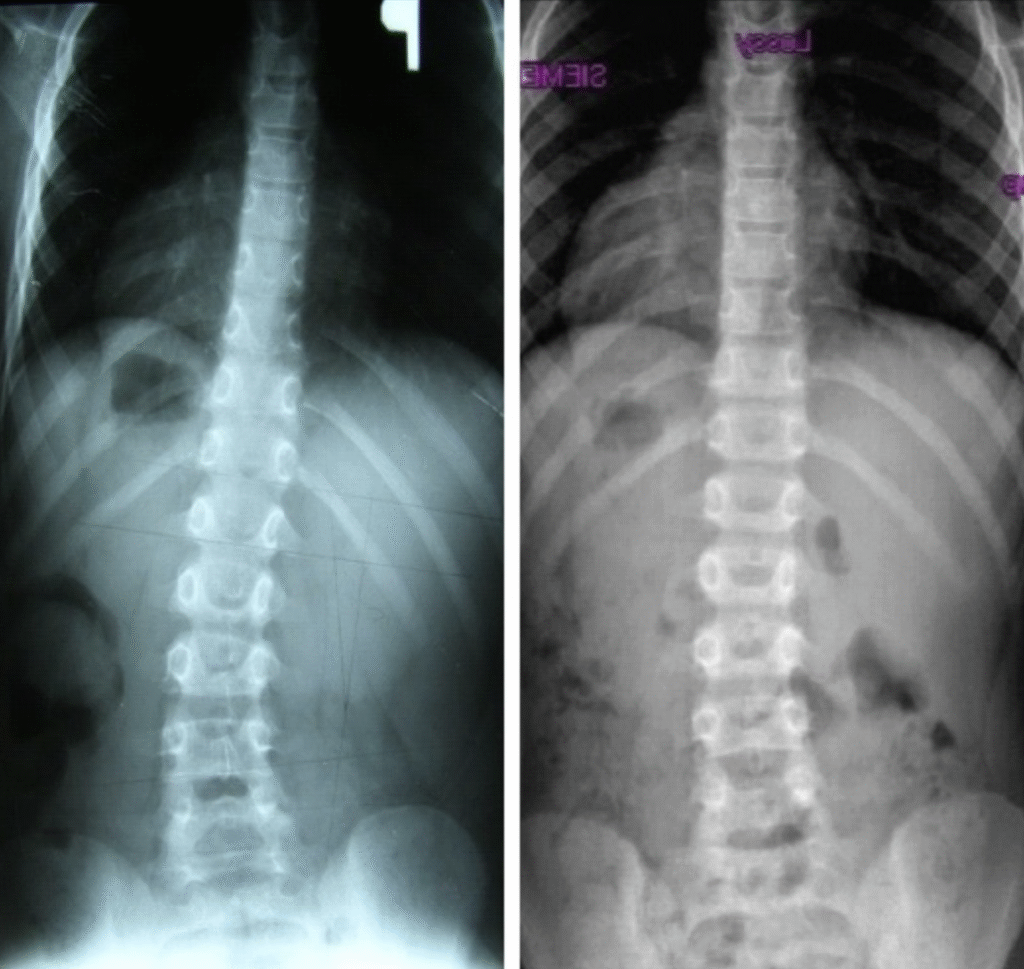

Piotr – 10 lat

Terapia prowadzona w okresie 15.09 – 01.12.2008 (20 zabiegów) Częstotliwość zajęć – 2 x tydz.

Justyna – 15 lat

Terapia prowadzona w okresie 02.08.2010 – 06.04.2011 (40 zabiegów) Częstotliwość zajęć – 2 x tydz.